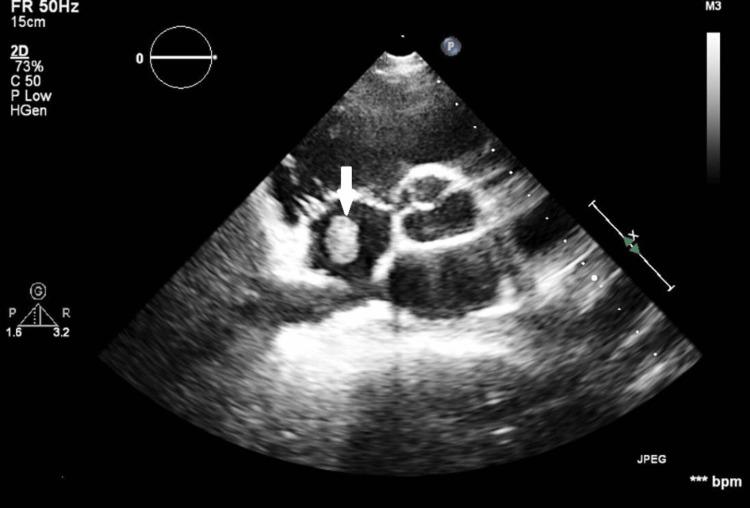

Systemic lupus erythematosus (SLE) is a multifaceted autoimmune disorder, occasionally presenting with rare complications like lupus enteritis (LE) and intestinal pseudo-obstruction (IPO). We present a unique case of a 32-year-old woman with LE and IPO, complicated by invasive candidiasis, as an initial manifestation of SLE. The patient presented with a 15-day history of abdominal pain, vomiting, and poor oral intake, and was initially misdiagnosed with infective enterocolitis. Examination revealed abdominal distension and absent bowel sounds due to IPO, alongside severe hypokalemia and signs of intra-abdominal hypertension (IAH), necessitating ventilator support. Subsequent workup confirmed SLE with LE and associated lupus nephritis (LN). The patient's condition was further complicated by disseminated invasive candidiasis involving multiple organs, including the bloodstream, chorioretinitis, and endocarditis. Despite her critical state, intensive multidisciplinary care, including high-dose steroids, antifungal therapy, and supportive measures, led to her recovery and discharge after a 51-day ICU stay. This case underscores the complexity of diagnosing SLE when it presents with non-specific symptoms. The concomitant occurrence of LE, IPO, and invasive candidiasis is particularly rare, highlighting the need for high clinical suspicion in the presence of SLE serological activity. The presence of invasive candidiasis was likely secondary to gut translocation due to LE-associated inflammation, a phenomenon not previously well-documented. LE can manifest as the primary and sole presentation of SLE, even in the absence of typical lupus features. Prompt immunomodulatory treatment and comprehensive care are essential for a favorable outcome. Clinicians should consider invasive candidiasis in SLE patients with acute GI involvement, particularly in the presence of LE.

系统性红斑狼疮(SLE)是一种多方面的自身免疫性疾病,偶尔会出现狼疮性肠炎(LE)和肠道假性梗阻(IPO)等罕见并发症。我们报告了一例独特的32岁女性病例,以LE和IPO为表现,并并发侵袭性念珠菌病,这是SLE的初始表现。患者有15天的腹痛、呕吐和进食减少病史,最初被误诊为感染性肠炎。检查发现由于IPO导致腹胀和肠鸣音消失,同时伴有严重低钾血症和腹腔内高压(IAH)体征,需要呼吸机支持。随后的检查确诊为SLE合并LE及相关狼疮性肾炎(LN)。患者病情因累及包括血液、脉络膜视网膜炎和心内膜炎在内的多个器官的播散性侵袭性念珠菌病而进一步复杂化。尽管患者病情危急,但包括大剂量类固醇、抗真菌治疗和支持措施在内的强化多学科护理使她在重症监护病房住院51天后康复出院。该病例强调了SLE以非特异性症状表现时诊断的复杂性。LE、IPO和侵袭性念珠菌病同时发生极为罕见,突出了在存在SLE血清学活动时需要高度临床怀疑。侵袭性念珠菌病的发生可能继发于LE相关炎症导致的肠道细菌移位,这一现象此前记录较少。LE可表现为SLE的主要和唯一表现,即使没有典型的狼疮特征。及时的免疫调节治疗和综合护理对于取得良好预后至关重要。临床医生应考虑SLE患者急性胃肠道受累时的侵袭性念珠菌病,尤其是在存在LE的情况下。